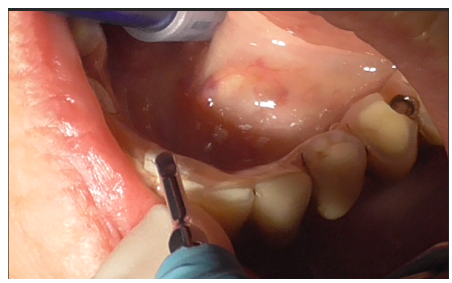

Removal of the prosthetic structure began by eliminating cement covering the prostethic abutment (Figures 3-5), followed by unscrewing the abutment (Figure 6) to facilitate the removal of the prosthesis.

Figure 3

Figure 4

Figure 5